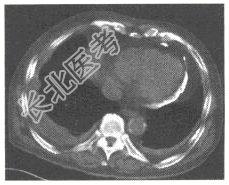

- [材料题] 患者,男,48岁。感呼吸困难、腹胀、乏力、头晕、咳嗽。查体心尖搏动不易触及,心音减低。下肢水肿。行胸部CT扫描如下图:

- 简答题1、图中钙化应考虑为?本病应诊断为?